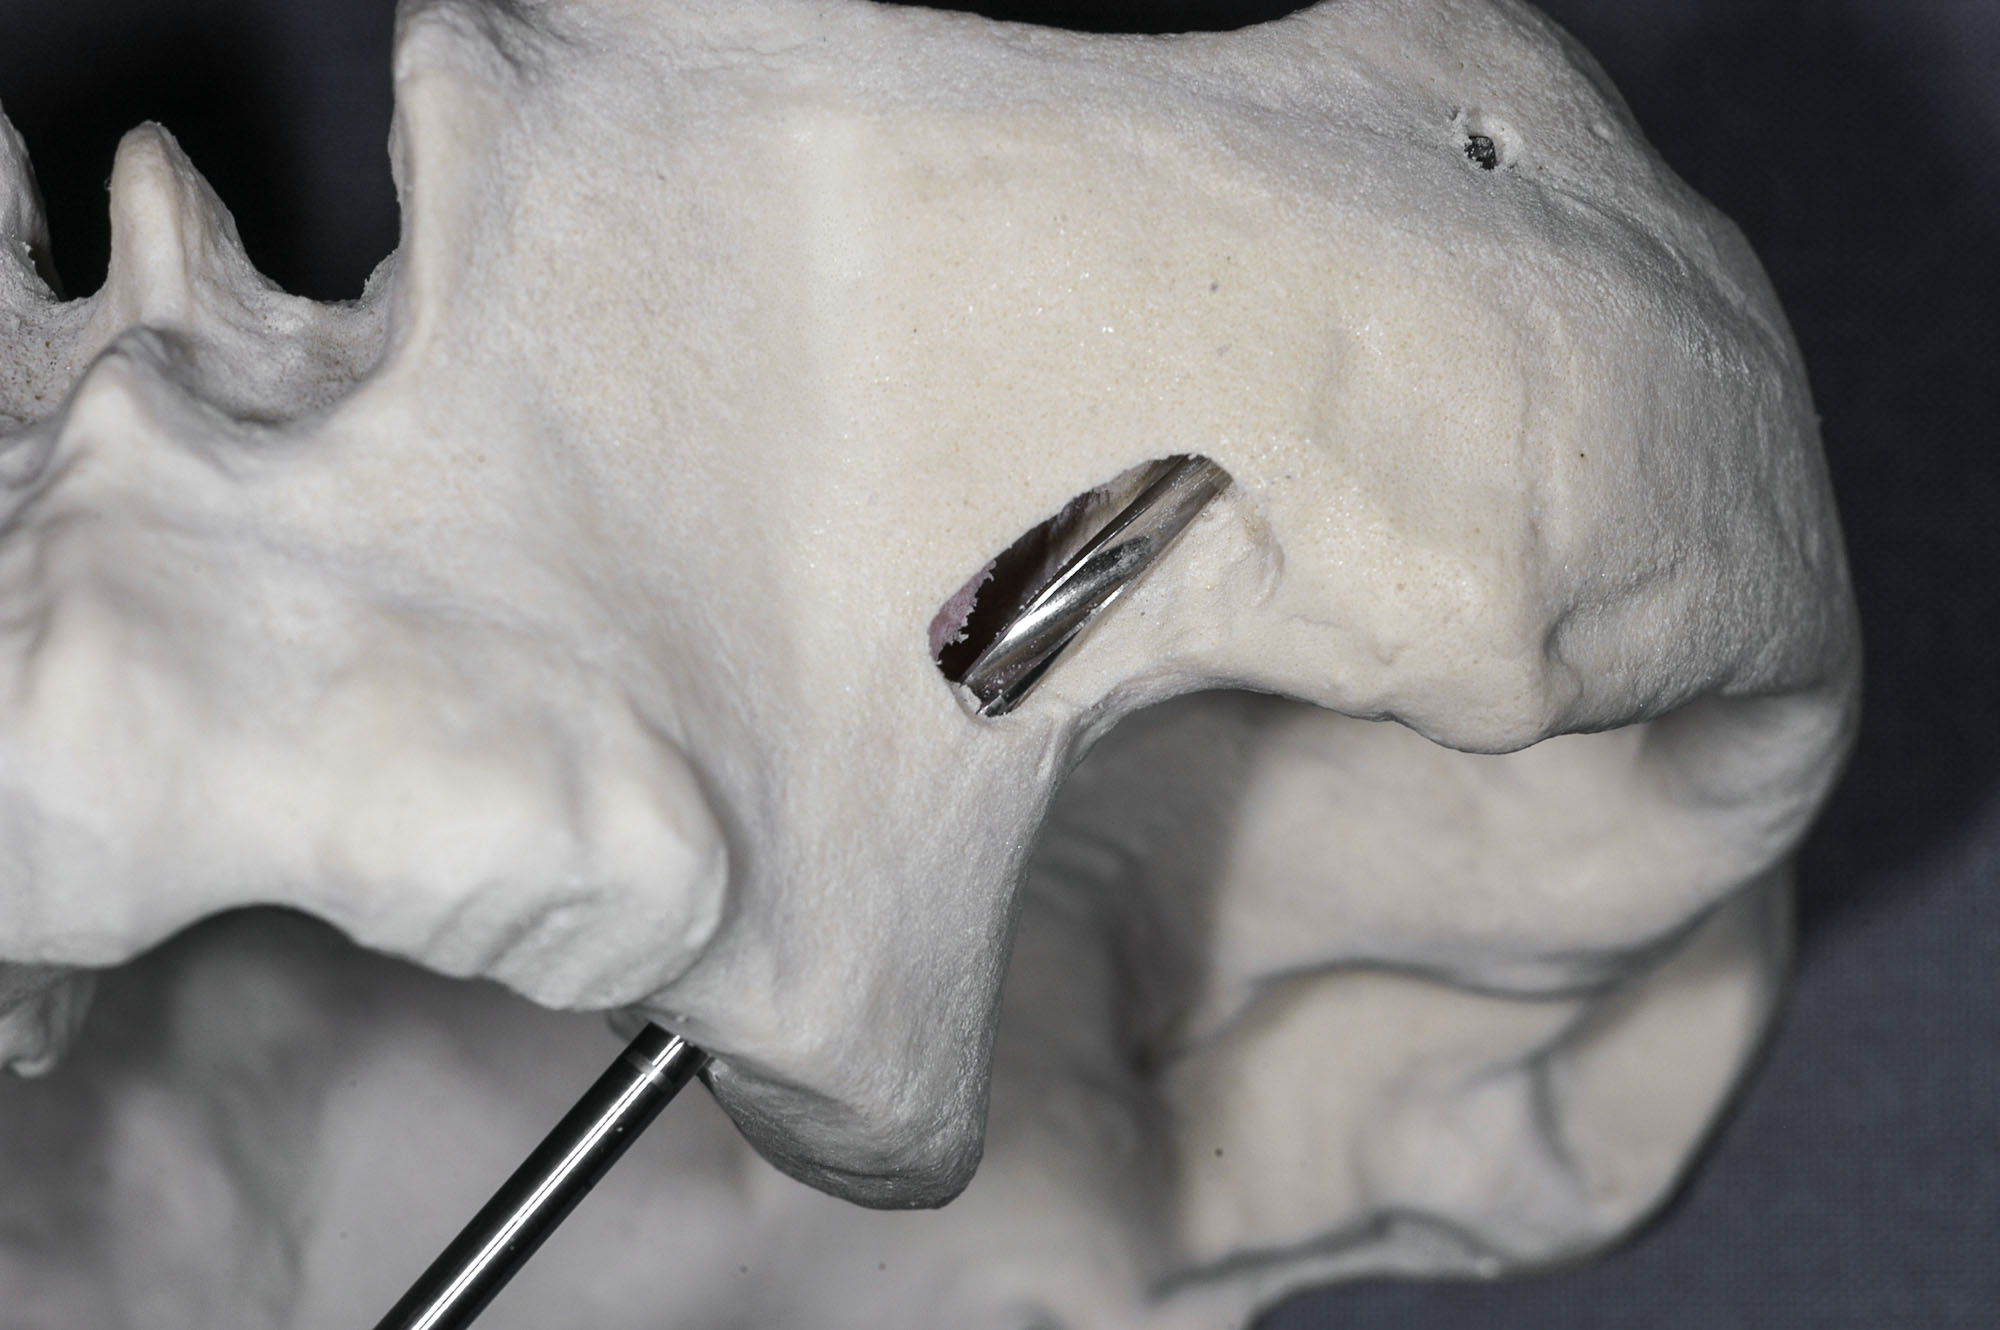

Na podstawie skanów CBCT można wydrukować modele kostne pacjenta w skali 1:1 w technologii FFF lub STL, co wydaje się szczególnie przydatne przy planowaniu zabiegu implantacji u pacjentów z ubytkami po resekcjach szczęk.